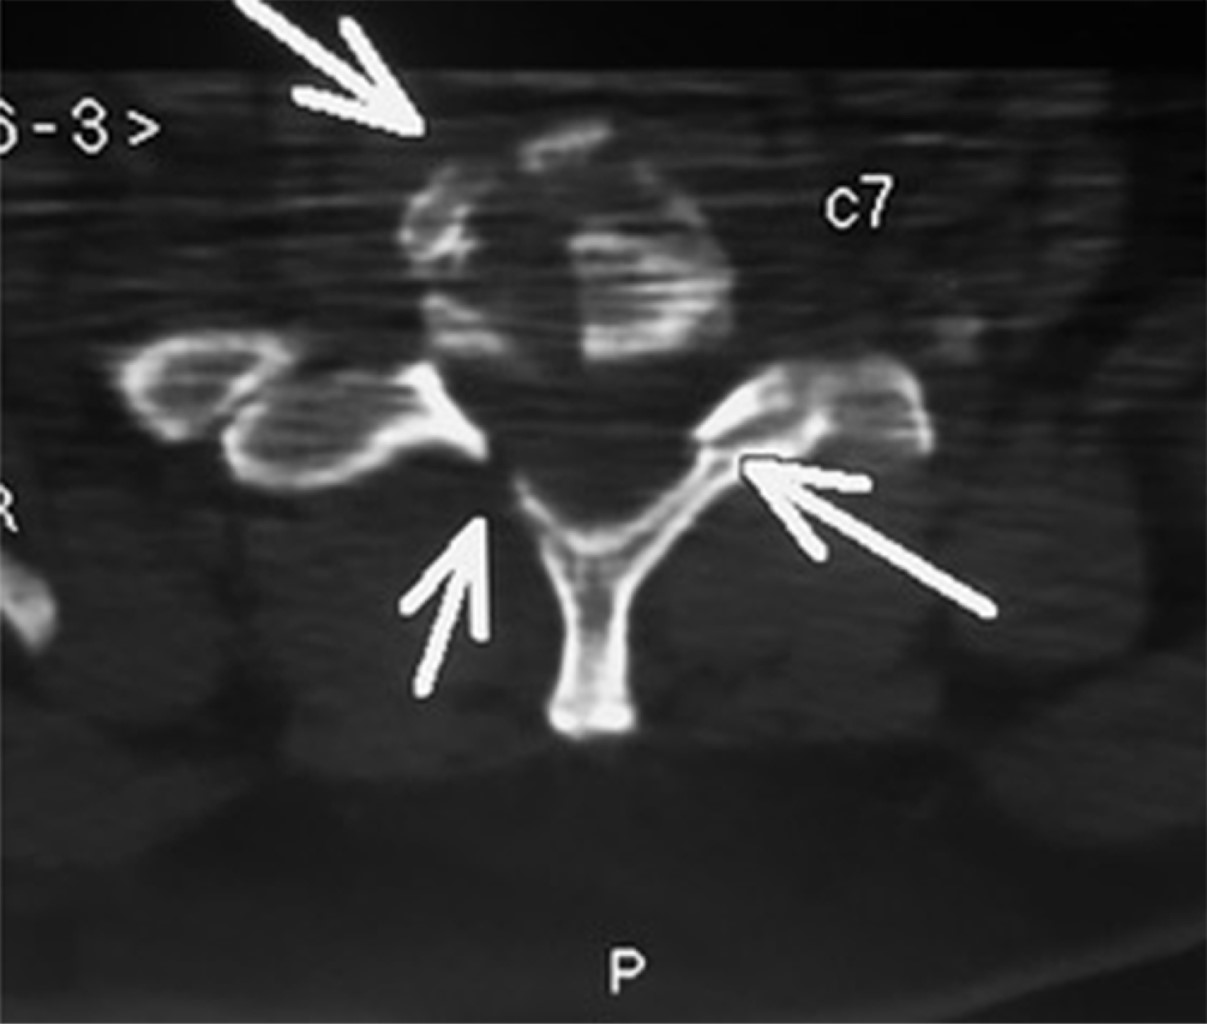

Paciente femenino de 46 años, se presenta en la sala de urgencias con politrauma secundario a accidente automovilístico. A su ingreso refería disnea, dolor de extremidades superiores e inferiores izquierdas y dolor cervical. A la exploración física se encontraba con inmovilización cervical con collarín rígido, saturación de oxígeno de 94% con mascarilla reservorio 10 L/min, presión arterial 74/52 mmHg, frecuencia cardíaca de 52 latidos por minuto, 18 respiraciones por minuto, Glasgow 15/15 con un peso de 88 kilogramos y estatura 1.54 metros (índice de masa corporal de 37.13). En el abordaje radiológico, la tomografía axial computarizada reveló una fractura multifragmentada de cuerpo vertebral de C7 con desplazamiento posterior cercano a 50% con disminución de la amplitud del conducto raquídeo (Figuras 1 y 2). Otros diagnósticos integrados fueron contusiones en hemitórax izquierdo, fracturas de tibia y peroné izquierdas y luxación de codo izquierdo.

Figura 1